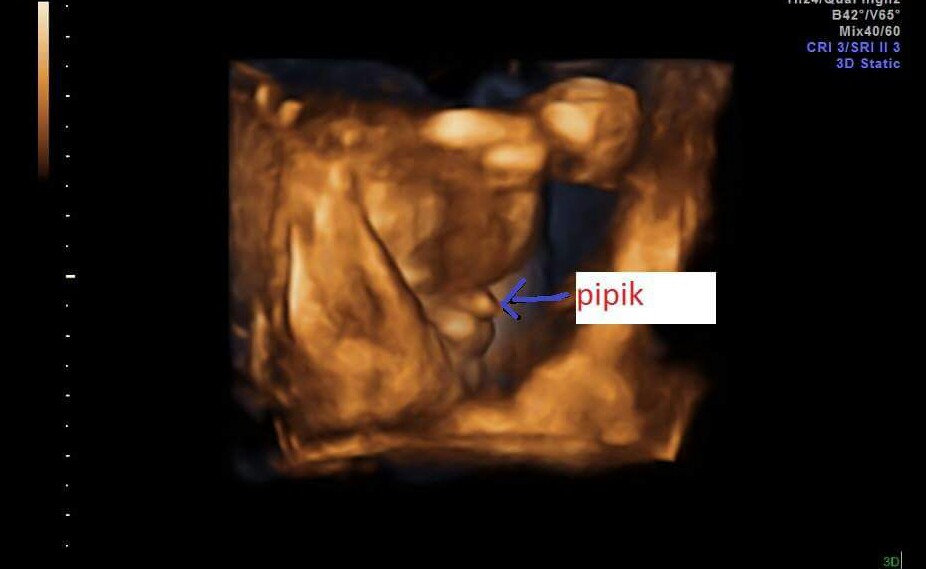

Teda ja som asi cudnb ale nieje to nostek?ja tam vidim tvaricku...🙂

autor@bambulalala nie nie to nieje nostek ten bol vyssie 😀 😀 😀

jeezis..to vazne je sulinek??😀..co ked to je zle potocena ruka?😀